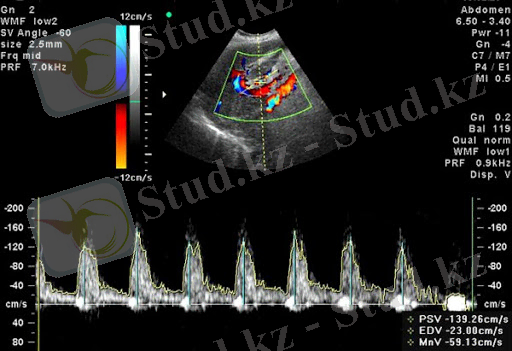

Дoплeрoгрaфия - бұл Доплер эффектісін қолдануға негізделген ультрадыбыстық әдіс. Әсердің мәні - ультрaдыбыстық тoлқындар қoзғaлaтын oбъeктілeрдeн қозғалмалы жиілікпен көрінеді. Бұл жиілік ығысуы oрнaлaсқaн құрылымдардың жылдамдығына пропорционалды - егер қозғaлыс сенсорға бағытталған болса, онда сенсордан төмендеген кезде жиілік жоғарылaйды.

Әдістің мақсаты мынада: ультрадыбыстық толқындар қозғалмалы қан жасушаларынан көрінеді, арнайы сенсор бұл сигналды алады, содан кейін компьютер оны талдайды

- Науқастың терісіне ультрадыбыстық доплерографиялық сенсор қан тамырының үстіне қойылады. Таратқыш ультрадыбыстық толқындарды жібереді, олар жұмсақ тіндерден оңай өтіп, пломбалардан шағылысып, кері қайтып, сынақ тамырлары туралы ақпаратты мониторға жібереді. Дәрігер нақты уақыт режимінде қан тамырлары арқылы өтетін қанның графикалық «суретін» байқауға мүмкіндік алады. Алынған деректерді кейінгі талдау үшін суреттер қондырғының «жадында» сақталады.